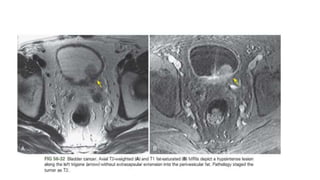

• #21 Papillary urothelial carcinoma (stage Ta) man. (a) On a CE CT scan Urographic phase images, dificult to make out the presence of a tumor. It is not possible to differentiate the tumor from the detrusor muscle. (b) Axial high-resolution T2-weighted MR image shows multifocal bladder tumors (black arrowheads). Note the chemical shift artifact, which appears as a thickened dark line along the lateral bladder wall (detrusor muscle) (arrow) and as a nearly imperceptible thin bright line on the contralateral side (white arrowheads). (c) On an axial three-dimensional (3D) spoiled gradient-echo (GRE) image obtained 20 seconds after contrast material injection, the multifocal bladder tumors show intense enhancement (arrowheads), unlike the muscle layer (arrow). (d) Axial 3D spoiled GRE image obtained 60 seconds after contrast material administration shows delayed enhancement of the muscle layer (arrow). Arrowheads = tumors.

• #22 Urothelial carcinoma (stage T2) man. (a)CE CT scan urographic phase imaging data shows a tumor (*) on the right lateral bladder wall. It is not possible to differentiate the tumor from the detrusor muscle. (b) Axial high-resolution T2-weighted MR image shows the tumor (*). Arrow = normal low-signal-intensity detrusor muscle, arrowhead = interruption of the detrusor muscle by the tumor in keeping with stage T2 disease. (c) Axial 3D spoiled GRE image obtained 20 seconds after contrast material administration shows the tumor (*), which has enhanced earlier than the muscle layer (arrow). (d) On an axial 3D spoiled GRE image obtained 60 seconds after contrast material administration, the detrusor muscle shows delayed enhancement (arrow), as well as interruption (arrowhead) by the tumor (*), findings that are consistent with stage T2 disease.